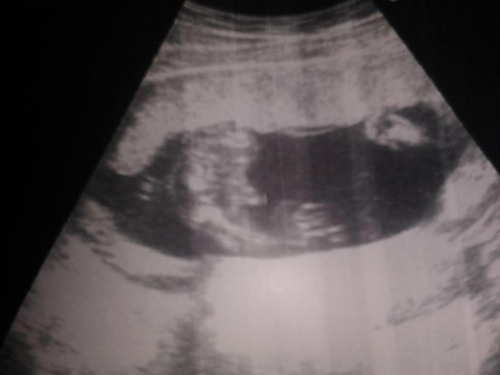

Wizyta super, z dzieciem wszystko w jak największym porządku, no i potwierdził się CHŁOPAK!

Mam równie bezwstydne dziecko co A.Kasia

Lekarz zwrócił uwagę, że Mały ma dosyć długą kość udową - jakby był tydzień starszy. Pewnie będzie chłop jak dąb po tatusiu (mąż ma 190 cm

) FHR 140, waga 245 g.

I rzeczywiście, tak jak pisały dziewczyny, dziecko już nie mieści się w kadrze, więc nie mierzy się dokładnie CRL, tylko ciężar.